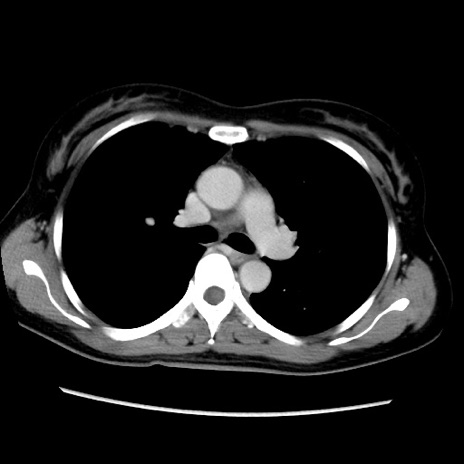

症例39(横断像)

【症例】40歳代女性

【主訴】上下腹部痛

【現病歴】2日目から下腹部痛あり。夜間は痛みで眠れなかった。昨日より上腹部痛と下痢が出現。臥位で痛みは軽快したため、休んでいた。本日になって臥位でも立位でも痛みが強くなってきたため救急要請。

【既往歴】子宮内膜症

【身体所見】部:平坦・軟、左上下腹部に圧痛あり、反跳痛あり。

【データ】WBC 21800、CRP 26.78